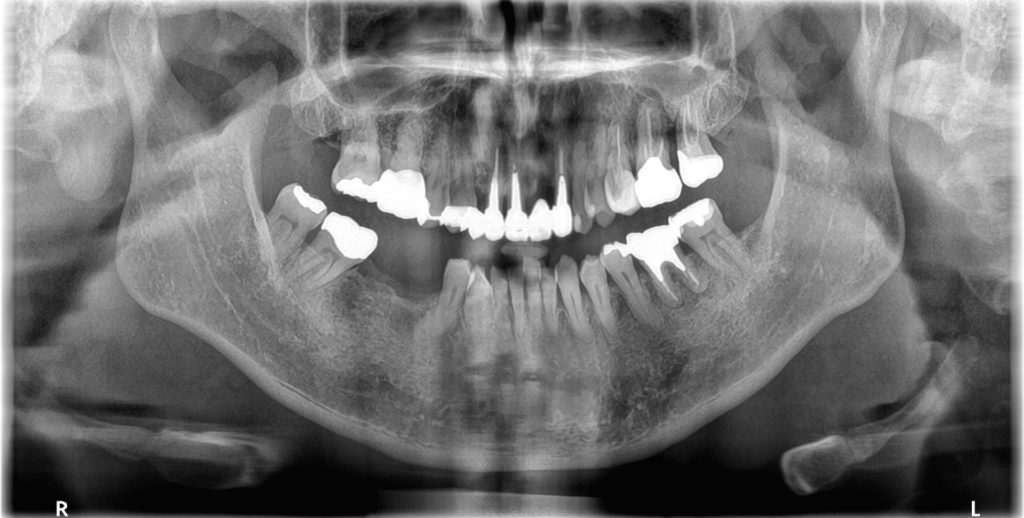

- パノラマレントゲン写真

そうですね、口腔内を拝見するとやや腫れていますね。レントゲンでもこの歯の周りには骨が溶けているように見えます。